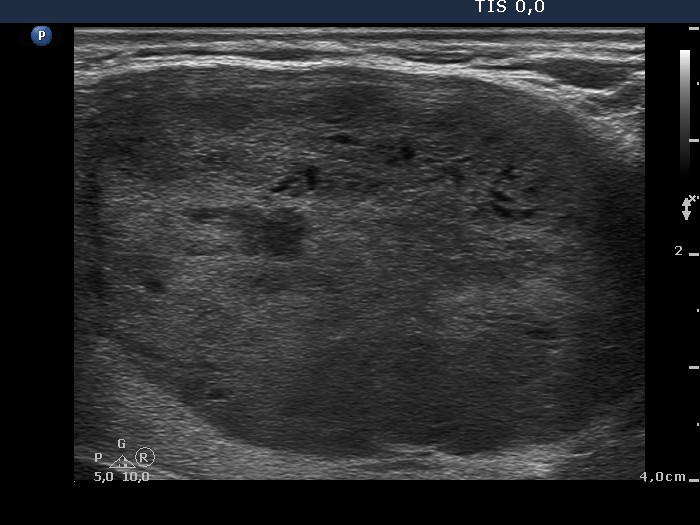

Ultrasonography. The thyroid was echonormal and presented several discrete hypoechogenic lesions. There was a large moderately hypoechogenic nodule in the isthmus. The nodule did not display halo but did perinodular blood flow.